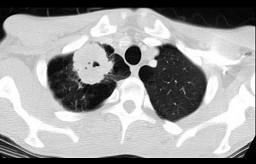

42岁,男,嗜烟酒,近一周咳嗽、咯血,请结合CT检查选择最可能的诊断 ( )A、韦格肉芽肿B、错构瘤C、肺癌D、肺曲菌病E、肺结核

问题 42岁,男,嗜烟酒,近一周咳嗽、咯血,请结合CT检查选择最可能的诊断 ( )

选项 A、韦格肉芽肿 B、错构瘤 C、肺癌 D、肺曲菌病 E、肺结核

答案 E